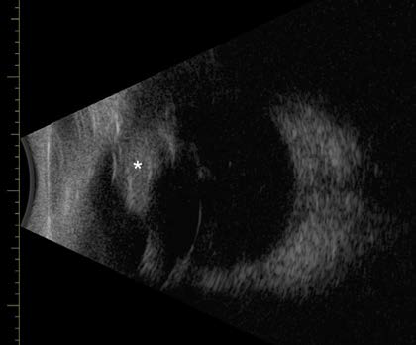

Complete ophthalmic examination revealed a large, dorsonasal, well-demarcated, intrairidal mass OS. A tan to pink intrairidal mass extending into the iridocorneal angle (case 1) and a pigmented intrairidal mass (case 2) were present. B-mode ultrasonography showed a focal, soft tissue, homogenous mass within the uvea adjacent to and contacting the lens. Neither pars plana involvement nor vitreal extension was present. A postero-anterior cyclo-iridectomy was performed through a polyhedral scleral flap. Thermocautery was used to complete the cyclo-iridectomy (case 1) and partial iridectomy (case 2) to excise the mass en bloc. Histopathology revealed a completely excised iridociliary adenoma (case 1) and iris melanocytoma (case 2). The surgery sites healed without complication. Mild uveitis (cases 1 and 2), scant vitreal hemorrhage (case 1), and mild hyphema (case 2) were present three days postoperatively but had resolved ten days postoperatively. The patients remain visual twenty-two months (case 1) and seven months (case 2) postoperatively with a normal intraocular examination other than an iridal defect and mild dorsonasal lens capsular opacities.